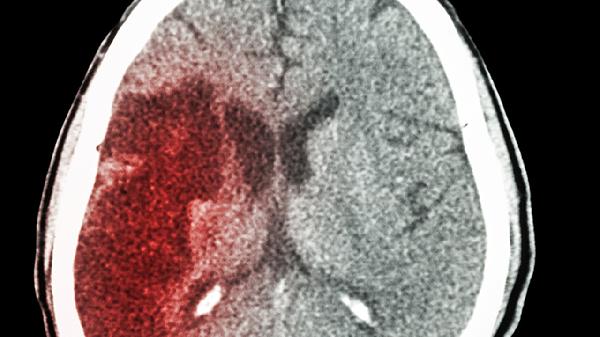

脑出血10ml属于中等量出血,恢复期可分为急性期、亚急性期和慢性期三个阶段。急性期约持续1-2周,以生命体征稳定和脑水肿控制为主,患者可能出现头痛、言语障碍或肢体偏瘫等症状。亚急性期持续1-3个月,此阶段脑组织开始修复,通过康复训练可改善运动功能和语言能力,部分患者需使用胞磷胆碱钠片、奥拉西坦胶囊等神经营养药物辅助恢复。慢性期持续3-6个月,多数患者功能恢复达到平台期,但仍需坚持肢体功能锻炼和认知训练,高血压患者需长期服用苯磺酸氨氯地平片等降压药物控制基础病。康复过程中若出现呕吐、意识模糊等新发症状需立即就医。